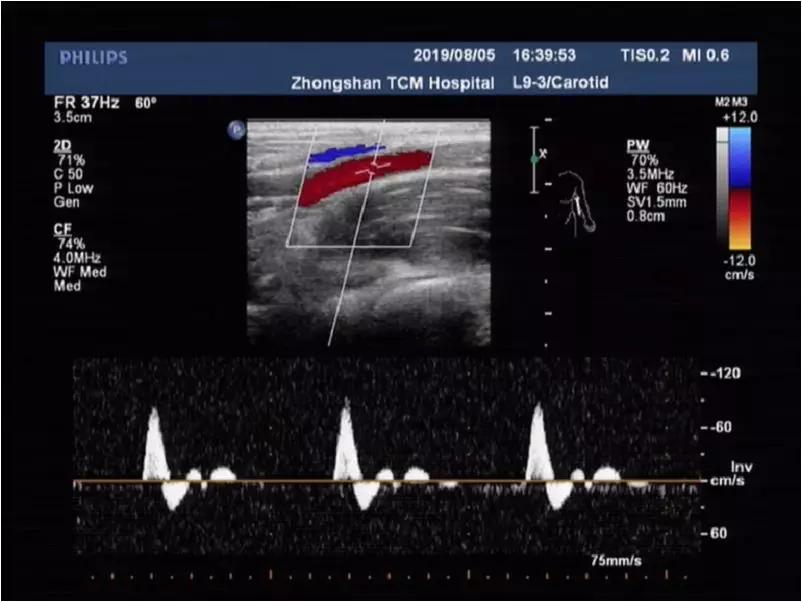

上举体位:上肢动脉频谱血流低速低阻,收缩期时相延长